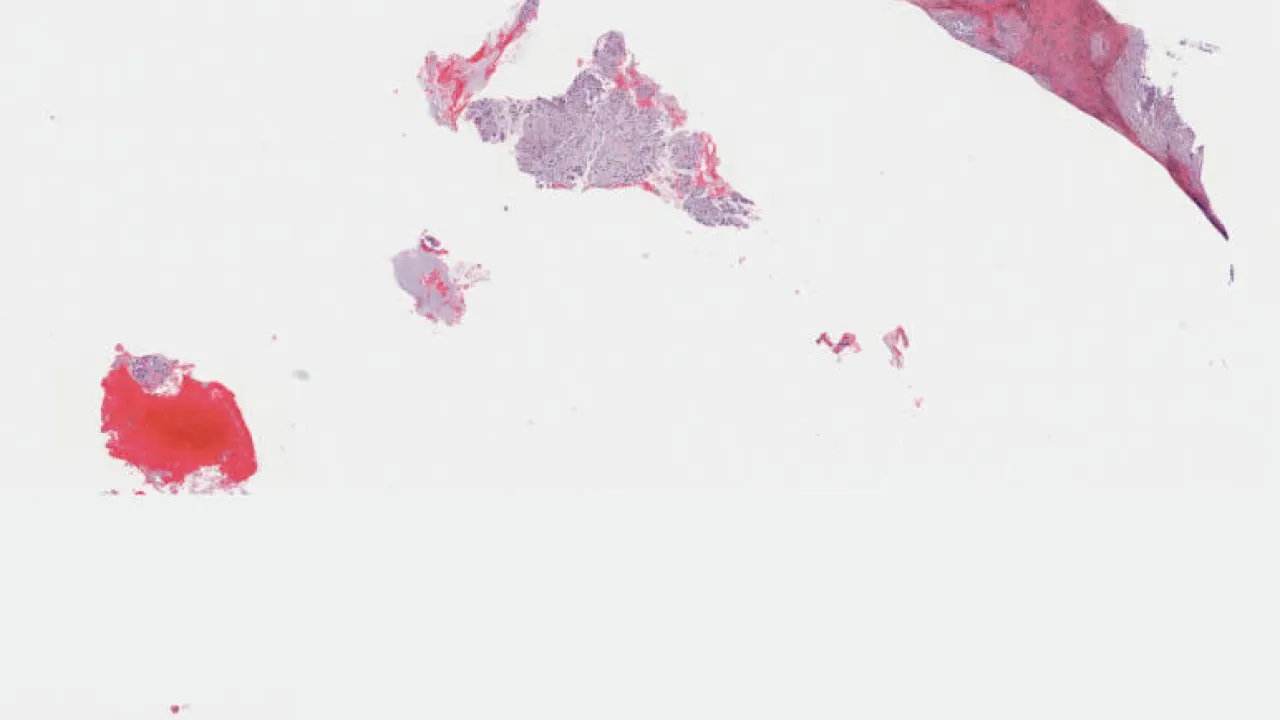

Ovary, yolk sac tumour, H&E stain